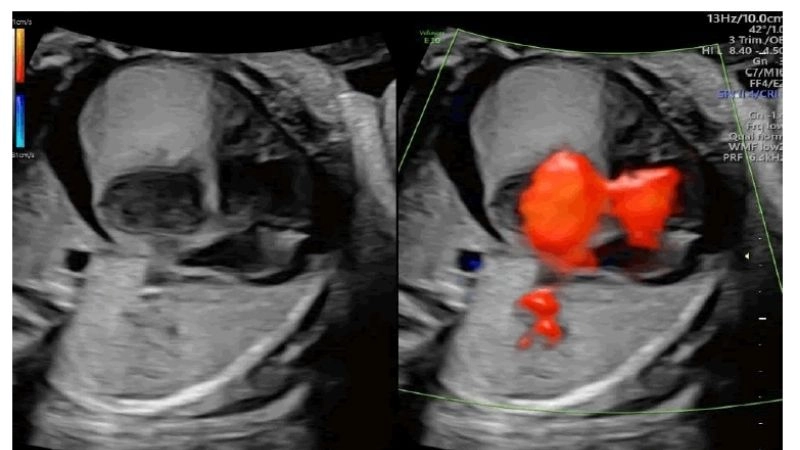

Images visual examples of rhabdomyoma

Rhabdomyoma is a rare benign tumor of striated muscle, commonly affecting the heart in children. Images often highlight cardiac masses that disrupt heart rhythm and function.

Insightful capture of fetal rhabdomyoma findings

Fascinating process of rhabdomyoma regression